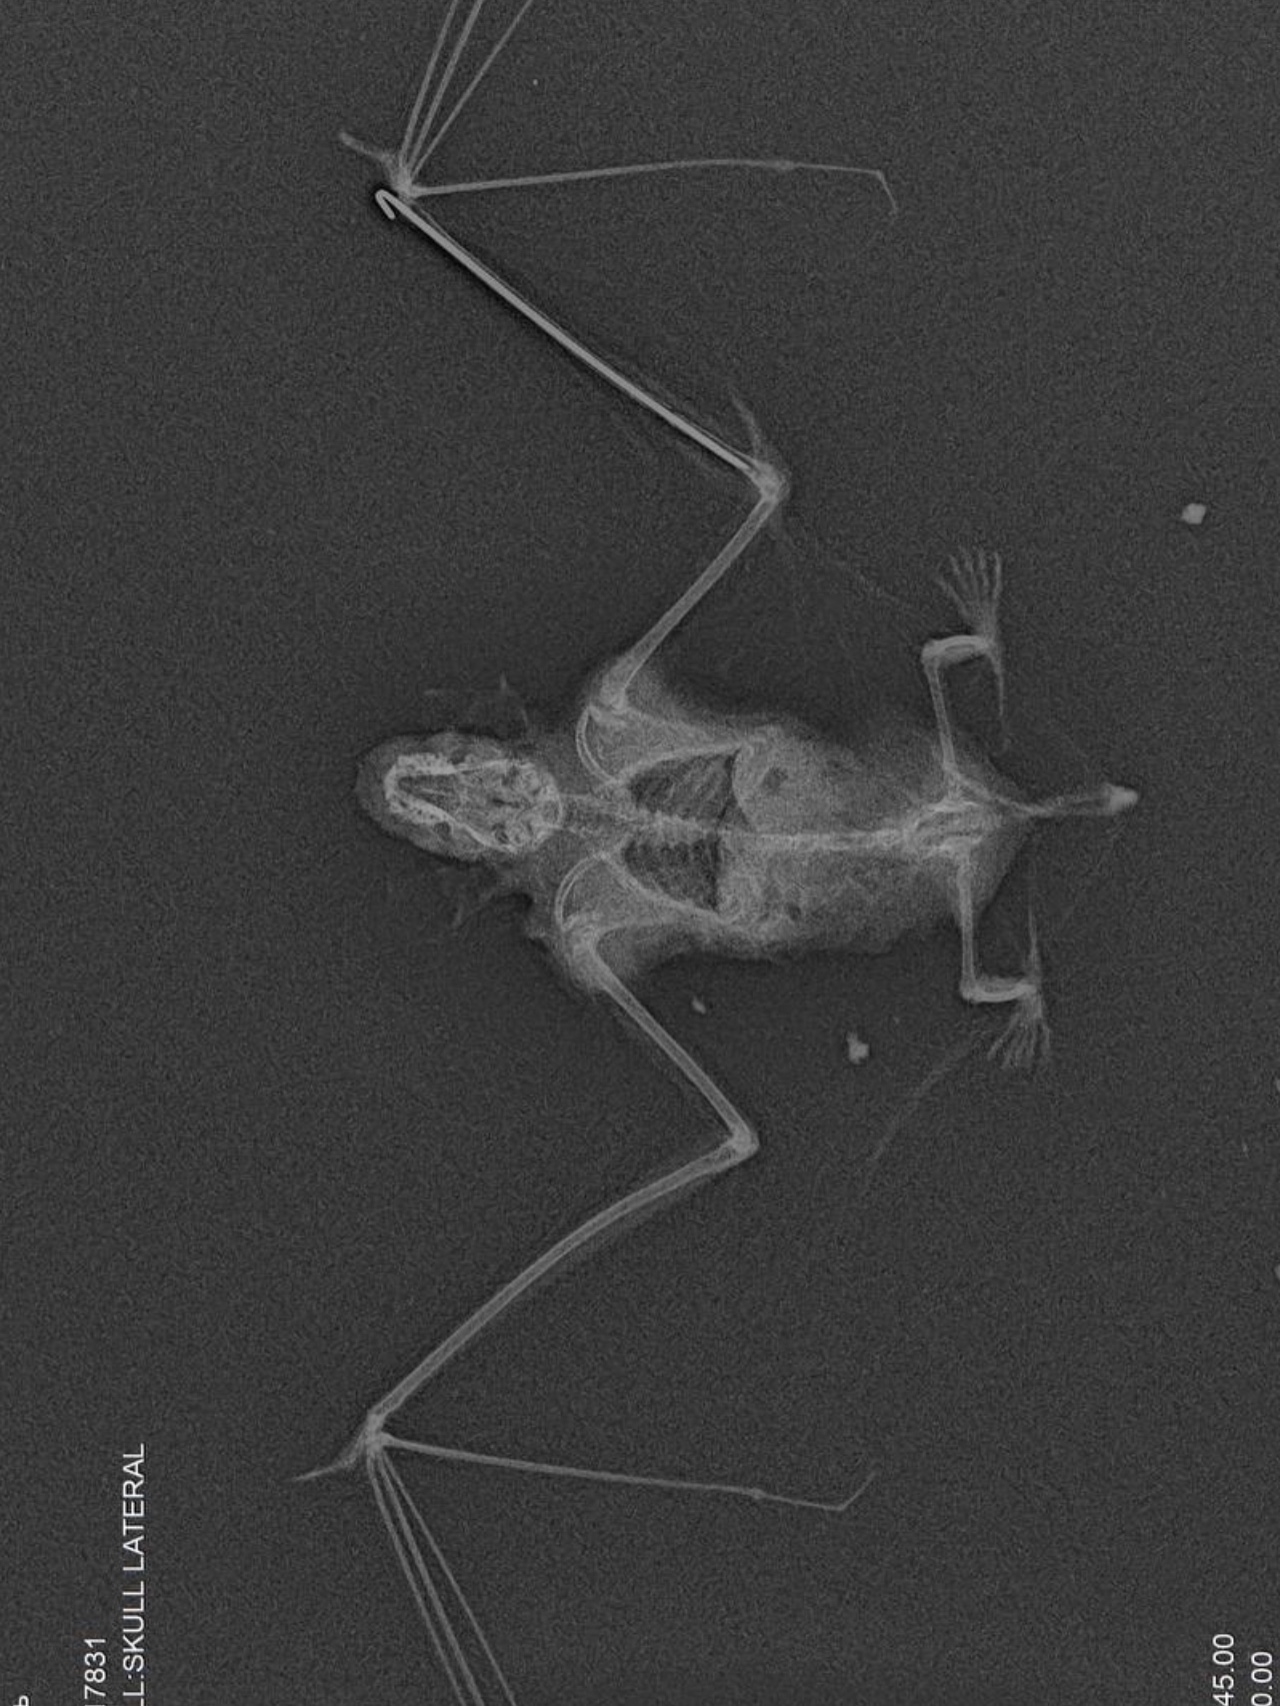

Клинический случай в клинике «Доктор Вет»: спасение летучей мыши.

Трофимова Ирина (в ВК Птерритория) доставила в клинику необычного пациента - двухцветного кожана с серьёзной травмой: на рентгене был обнаружен перелом предплечья. Возраст пациента был определен по состоянию зубов - весьма почтенный.

При минимальном размере кости всего в 1 мм было выполнено ювелирное вмешательство - остеосинтез перелома предплечья.